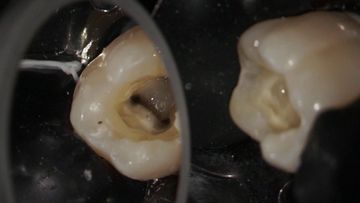

/education-service/media/default/68493/6cbd3e79.jpg)

13min

Lesson

Complete molar endodontic treatment & full rotary instrumentation

Radu Brata

Clinical Video